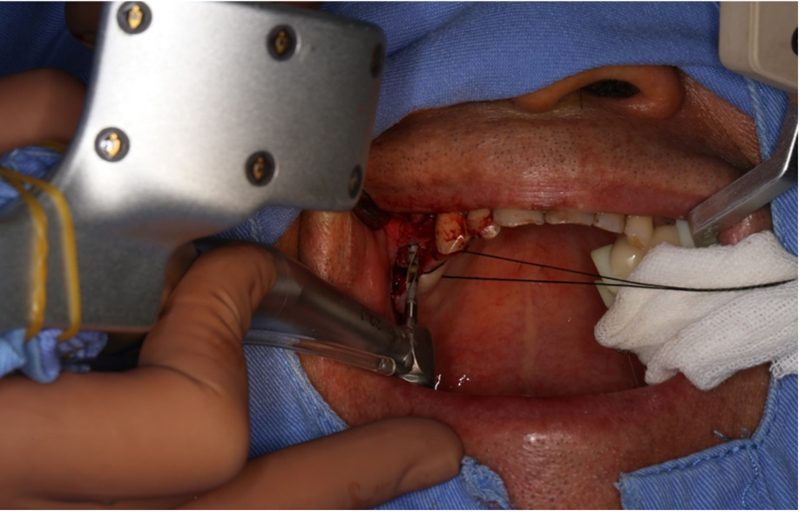

®按照術前方案進行備洞及植體植入

®按照術前方案進行備洞及植體植入,醫(yī)生可以通過屏幕軟件引導對手術中植入點、角度、深度實時追蹤

®對植體深度及方向進行確認

®完成3顆植體的植入,植體位點如術前方案設計,均在同軸線。

®進行縫合